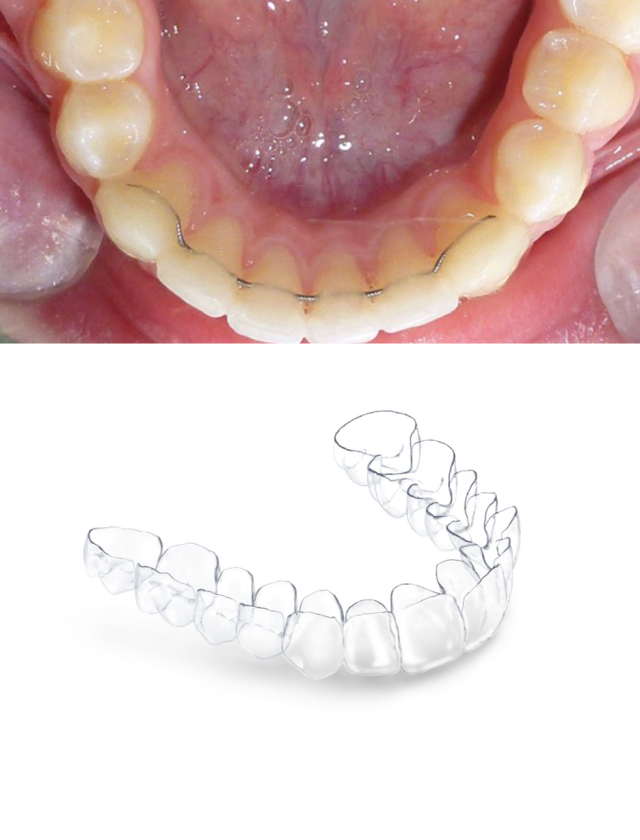

contention

La contention et le suivi post-traitement

La contention est l’ensemble des procédés permettant de s’opposer à la récidive, en stabilisant les corrections orthopédiques et orthodontiques obtenues pendant le traitement. C’est la phase thérapeutique finale du traitement orthodontique.

• Porter de façon rigoureuse un système de contention adapté à chaque cas :

• Fixe : fil de contention collé derrière les incisives et canines

• Amovible : gouttière thermoformée

Ce système de contention sera à porter le plus longtemps possible, voir à vie, afin d’éviter tout risque de récidive et que les dents ne rebougent.